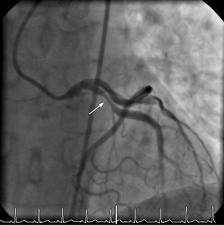

Depending on the results of the above tests, your doctor may suggest that you have other tests such as coronary angiography or an electrophysiological study (EPS). Both these tests are performed in an X-ray laboratory that allows the body and any medical tools (such as cardiac catheter tubes or pacing wires) to be seen using an X-ray camera. You will be asked to lie down on a special moving table and will be given a local anaesthetic in your groin. The doctor will then place fine tubes, called cardiac catheters or electrodes, into blood vessels in your groin. These are gently passed through to the heart. During coronary angiography the coronary arteries (the arteries that supply blood to the heart muscle) are injected with a dye to reveal any furring or blockages – coronary artery disease. (The ECG changes that are characteristic of Brugada Syndrome or LQTS can sometimes be caused by coronary artery disease.)